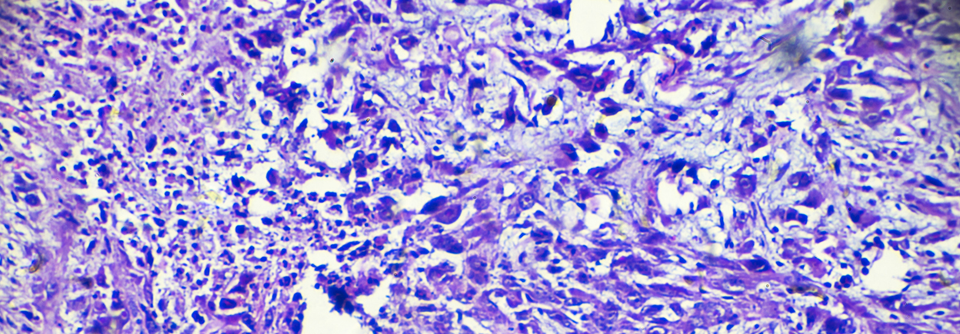

NSCLC: Checkpoint-Inhibition plus Chemotherapie wirksam bei PD-L1-Expression von 1–49 %

Acht zulassungsrelevante NSCLC-Studien zu Immuntherapien analysierte die FDA. Ihr Fazit: Bei den meisten Patienten mit NSCLC-Tumoren und einer…

mehr

Onkologie und Hämatologie , Pneumologie ASCO 2021

Reserzierbares NSCLC: Nivolumab zusätzlich zur Chemotherapie als sinnvolle Option

Checkpoint-Inhibitoren dringen beim nicht-kleinzelligen Lungenkarzinom jetzt auch in frühere Krankheitsstadien vor: In der Phase-3-Studie…